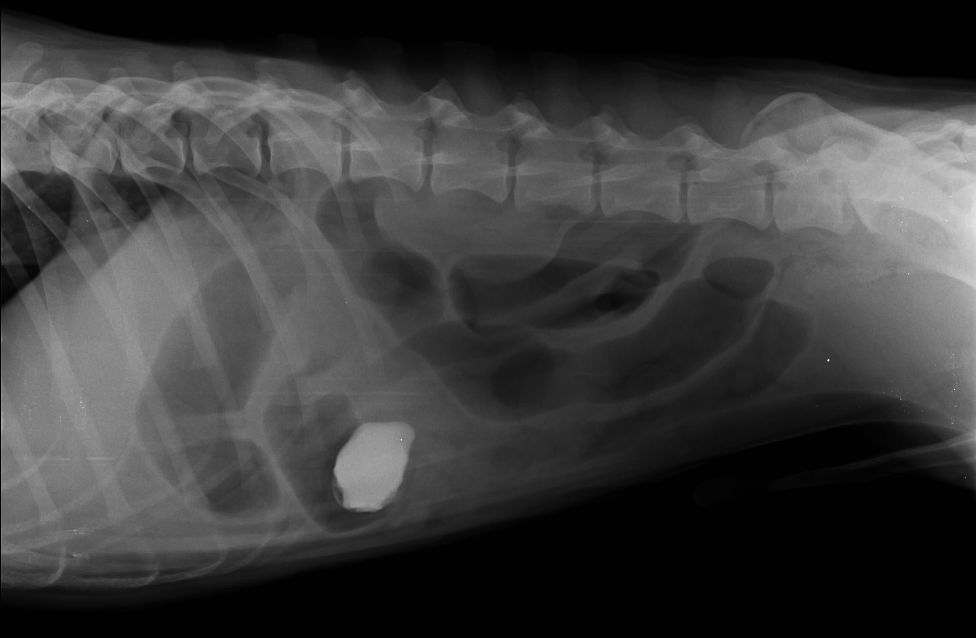

Esta herramienta diagnóstica es de suma importancia, ya que a través de sombras de diferentes tonos podemos ver los contornos de diferentes órganos. Entre otra cosas, es muy útil en en la evaluación del tórax, permite diferenciar los detalles de los pulmones, pleura, corazón, etc. Igualmente a nivel de la columna y otras articulaciones, como es el caso de la cadera (art. coxofemoral), podemos definir lesiones crónicas, lesiones congénitas y considerar un tratamiento. Especial utilidad cuando existen fracturas, según su comportamiento y extensión se definirán los métodos de reducción mas adecuados.

Radiografías simples

Radiografia digital simple y con contraste